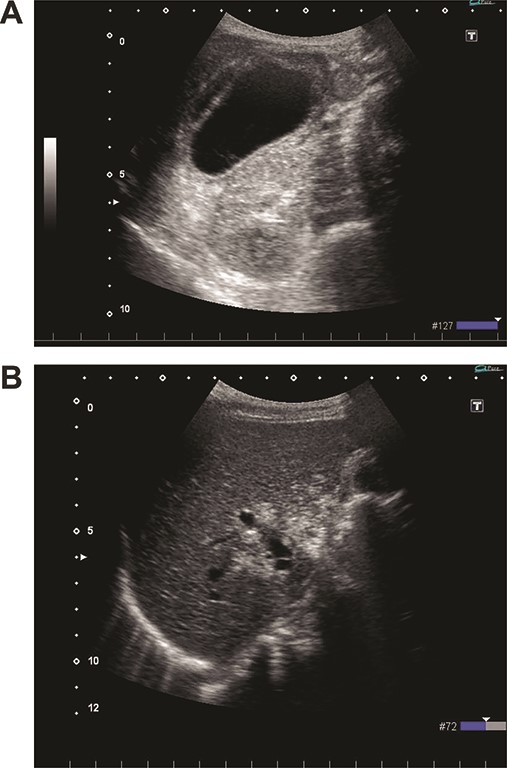

On admission, her vital signs were normal. Her medical history included dermatomyositis, hypertension and osteoporosis. She had a white blood cell count of 10.6 × 103/μL, hemoglobin of 8.2 g/dL and lactic acid of 0.8 mmoL/L. A physical examination demonstrated strong tenderness in her right upper quadrant abdomen. Ultrasonogramphy (US) showed diffuse wall thickening of her gallbladder without cholecystolithiasis. US also revealed small mobile echogenic foci moving inside the portal venous branches (Fig. 1). The hyperechogenic foci were seen in the middle segment and right anterior segment of the liver. Contrast-enhanced computed tomography (CT) showed a diffusely thickened wall of the gallbladder with poor enhancement, suggesting acute necrotizing cholecystitis (Fig. 2). Tiny bubbles were seen in the intrahepatic portal venous branches (segment 4 and segment 5), but there was no evidence of bowel ischemia. She was then diagnosed with necrotic cholecystitis and immediately underwent emergency operation.

(A) Ultrasonography shows distention and wall thickening of the gallbladder. (B) Ultrasonography shows small mobile echogenic foci and hyperechogenic linear structures in the middle segment and right anterior segment of the liver.